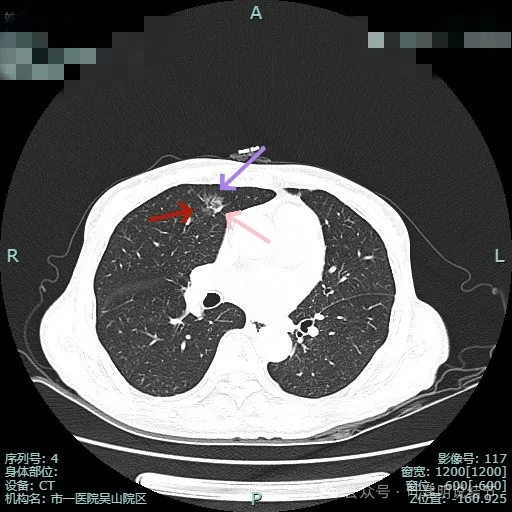

毛刺明显,灶内小血管走行,表面分叶,轮廓清楚,瘤肺边界清。

细毛刺典型而锐利;灶内有实性成分;整体轮廓清,灶内细支气管扩张通气。

上图明显感觉到收缩力,月牙铲征以及灶内细支气管扩张、锐利短细毛刺,整体轮廓与边界清,很典型恶性。

病灶较小了些,但给人感觉收缩力仍强,细支气管有扩张与截断。

边缘区小片状,但仍有收缩力与边界较清。

条索区域了,仍有毛刺征,纵隔侧有轻微胸膜牵拉。

边缘区磨玻璃条状,也有毛刺样征。